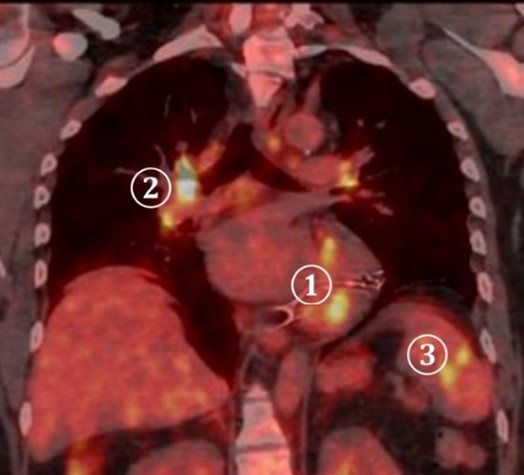

För närmare kartläggning av inflammationens utbredning utförs PET-DT

Tolka bilderna. Vilka anatomiska strukturer ”lyser” (inflammation/ämnesomsättning)?

- Ökat FDG-upptag i

- Hjärta ①

- Hiluslymfkörtlar ②

- Mjälte ③

- Isotopen utsöndras via njurar